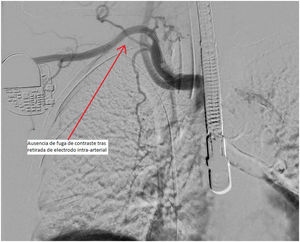

Tras la inserción y comprobación del correcto funcionamiento del electrodo nuevo y mediante el uso de escopia intraquirófano, se lleva a cabo por parte de cirugía vascular la introducción de una guía vía arterial (axilar derecha), la cual tras la retirada del electrodo transaórtico por tracción simple, se utiliza para comprobación de extravasación sanguínea mediante el uso de solución de contraste, evidenciándose ausencia de sangrados activos (fig. 5). Tras unos minutos y una vez finalizado el procedimiento se constata ausencia de pulso radial ispilateral por lo que se decide realizar trombectomía abierta recuperándose así pulso cubital, y finalizando el procedimiento sin más incidencias.